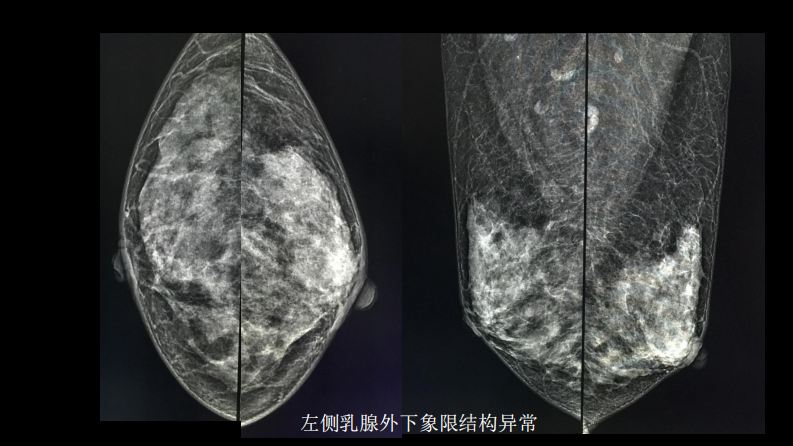

乳腺囊性肿块MRI:鉴别不困难.pdf

乳腺